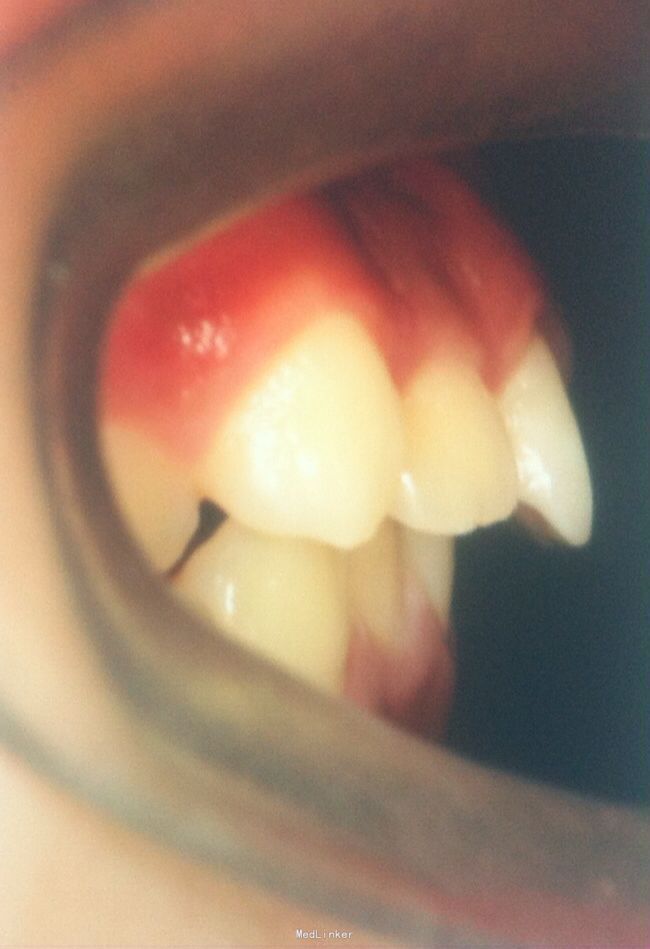

恒牙期 33,44唇侧错位 磨牙中性关系 前牙覆合2度、覆盖1度 牙列拥挤

牙列拥挤、安氏一类 拔牙矫治,拔除14、24、34、44(强支抗)排齐整平上下牙列,直丝弓矫治器,关闭拔牙间隙,矫治后前牙覆合覆盖正常,磨牙中性关系,面型略改善